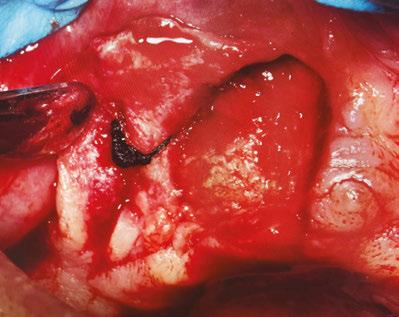

On the day of the surgery, before commencing the procedure under strict asepsis, the patient was asked to rinse with 0.12% chlorhexidine gluconate mouthwash (Peridex™; 3M™). Local anesthesia with a vasoconstrictor was infiltrated buccally and palatally into the posterior and anterior maxilla on both the sides using S-blades (straight) (Zabby, India). The incision was made

on the crest of the ridge in the region of teeth Nos. 15-25. While creating the incision, bleeding was noticed in the region of tooth No. 15 which intensified during the flap reflection (Figure 2). Bleeding was pulsatile, indicating an arterial bleed. Initially attempts to control bleeding included a pressure pack and ice pack, and the bleeder was isolated, and the vessel ligated (Figure 3). The bleeding could be controlled, and the procedure was completed by placing four Bioner implants (Bioner, Spain), size 4/10 mm. Sutures were placed, and patient was kept on basic medication for pain and infection control. Immediately after the surgery, the patient was advised to get a CBCT. As shown in Figure 4, a coronal view and Figure 4B (yellow arrows), the position of the artery can be seen.

Figure 1: Pre-op panoramic radiograph Figure 2 (left): Alveolar antral artery (AAA). Figure 3 (center): The artery has been ligated with suture. Figures 4A and 4B (right): CBCT post-implant placement and position of the artery coronally (top). 4B. Showing the position of alveolar antral artery (AAA) in relation to implant placement as indicated by the yellow arrows (bottom)